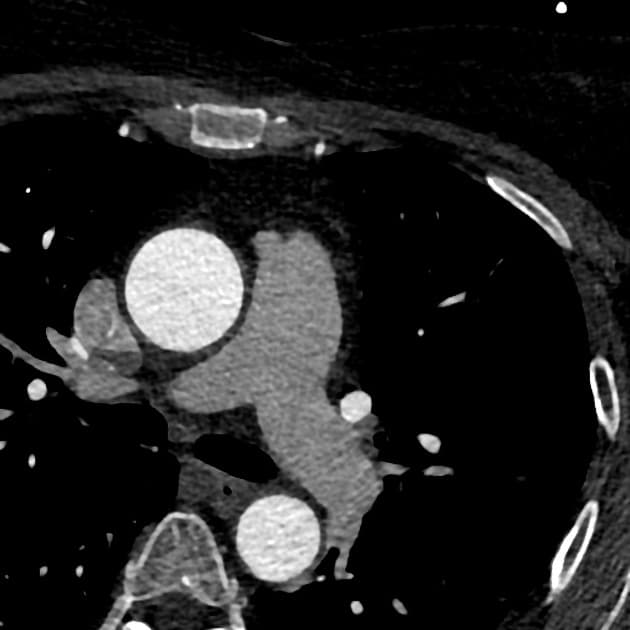

Có một khối mô mềm giới hạn không rõ (ill-defined soft tissue mass) gần như chiếm toàn bộ tâm nhĩ trái, xuyên qua vách liên nhĩ vào tâm nhĩ phải và dường như lồi vào tĩnh mạch chủ dưới (inferior vena cava - IVC) gần đoạn đầu. Khối này có độ cản âm tương đối đồng nhất (homogeneous hypoattenuation). Không thấy tăng quang đáng kể, không thấy hình ảnh hoại tử trung tâm hay vôi hóa.

Cũng ghi nhận tràn dịch màng ngoài tim mức độ trung bình, đo được độ sâu tối đa 4 cm, chủ yếu tập trung dọc theo bờ dưới của tim; chưa rõ có tổ chức đặc không tăng quang trong khoang màng ngoài tim hay không.

Đoạn gốc tĩnh mạch phổi dưới trái bị hẹp nhẹ. Nhánh sau bên của động mạch vành phải dường như bị bao quanh bởi mô mềm.

Kết luận: Hình ảnh phù hợp với khối u tim khu trú ở tâm nhĩ trái, xuyên qua vách liên nhĩ vào tâm nhĩ phải, kèm tràn dịch màng ngoài tim và lan vào tĩnh mạch chủ dưới (IVC extension). Đặc điểm này không điển hình cho myxoma nhĩ; cần cân nhắc sarcoma, di căn (metastasis), lymphoma hoặc huyết khối (thrombus).

Trên cộng hưởng từ (MRI): khối tổ chức mềm đồng tín hiệu T1 (T1 isointense) và tăng tín hiệu nhẹ trên T2 so với cơ, có tính chất xâm lấn, khu trú ở phần dưới tâm nhĩ trái, xuyên qua vách liên nhĩ vào tâm nhĩ phải và lan ra ngoài vòng van hai lá vào thành thất trái dưới phần nền. Thành phần nhỏ dạng thùy, dạng lá ở tâm nhĩ phải di động nhẹ, không sa xuống thất phải. Không thấy tăng tín hiệu trên T1 để gợi ý mỡ trong khối.

Chụp tưới máu (perfusion imaging) cho thấy khối kém tưới máu (hypovascularity), tăng quang nhẹ trên cả hình ảnh gadolinium sớm và muộn. Chức năng thất trái bình thường, phân suất tống máu 62%. Không thấy thành phần đặc trong tràn dịch màng ngoài tim mức độ trung bình đến nhiều.

Kết luận: Khối mô mềm kém tưới máu (hypovascular), tăng quang nhẹ, đồng tín hiệu T1 và tăng tín hiệu nhẹ trên T2 so với cơ, khu trú ở tâm nhĩ trái, xâm lấn qua vách liên nhĩ vào tâm nhĩ phải và qua vòng van hai lá vào thành nền thất trái dưới. Tràn dịch màng ngoài tim mức độ trung bình, không có hình ảnh cộng hưởng từ gợi ý chèn ép tim (tamponade).